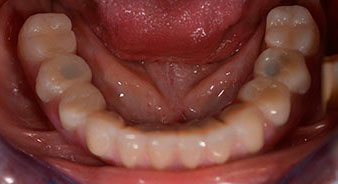

След това е взет отпечатък и е определена захапката на пациента, за да може зъботехникът незабавно да започне изработването на временната протеза. Протезата е поставена в същия ден (Фиг. 17 и 18).

След изчакване на необходимото време за осеоинтеграция, финалният отпечатък на имплантите е свален и следователно е изработена финалната протеза (Фиг. 19 и 20). В този момент, лекарят по дентална медицина и пациентът могат да обсъдят дали да използват керамични или пластмасови фасети и циркониева или метална рамка. В този случай, екипът на д-р Паску избира пластмасови фасети, имайки предвид неясната прогноза относно частичното обеззъбяване в челюстта и фактът, че зъб 24 е прорастнал. Този вид протеза обикновено е по-лесна за адаптиране и впоследствие може да бъде променяна спрямо новата ситуация в челюстта.